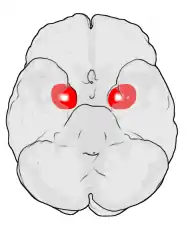

Sexo y diferencias hemisféricas

Hay evidencias en muchas especies de que la amígdala está muy involucrada en la respuesta a las hormonas sexuales. La amígdala contiene receptores tanto para estrógenos como andrógenos y responde a fluctuaciones en los niveles hormonales mediante cambios en su morfología. La amígdala es mayor en varones adultos tanto en humanos como en muchos roedores y las hormonas parecen ser capaces de alterar muchas características de la amígdala, incluidas el número de neuronas y la expresión de sus neurotransmisores.

Además, resultados recientes sugieren que las diferencias sexuales en la amígdala podrían correlacionarse con diferencias hemisféricas de la amígdala. Cahill y otros[6] sugieren una teoría «derecha-varón, izquierda-mujer» de la actividad de la amígdala. Así, las conexiones con la amígdala derecha facilitan un mejor seguimiento o vigilancia de estímulos externos, y las conexiones con la amígdala izquierda facilitan un mejor seguimiento o vigilancia de estímulos internos.